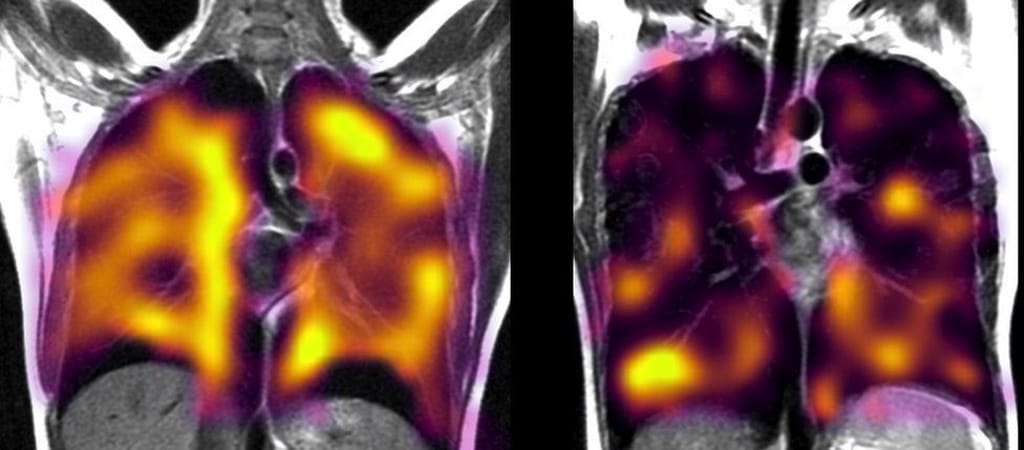

A kutatók a Sheffieldi Egyetem úttörő módszerét használták, ami abból állt, hogy a pácienseknek egy veszélytelen anyagot, xenongázt kellett belélegezniük. A színtelen, szagtalan vegyület az oxigénhez nagyon hasonlóan viselkedik, ám vele ellentétben ez vizuálisan nyomon követhető az MRI-típusú berendezésekkel. Azért azokkal, mert a CT- és röntgen-vizsgálatok erre nem alkalmasak, azok ugyanis csak a tüdő szerkezetét mutatják.

A szakértők azt találták, hogy a hosszú Covidban szenvedőknél (akiknél tehát a légszomj tünete továbbra is fennállt), a gáz nem jut olyan hatékonyan a tüdőből a véráramba. Úgy vélik, hogy ez a szerven keletkezett mikrokárosodásokra vezethető vissza, míg utóbbiak a fertőzésre, illetve az utána következő betegségre. A kutatók a long Coviddal nem diagnosztizált, de kórházba került pácienseknél is hasonló rendellenességeket tapasztaltak.